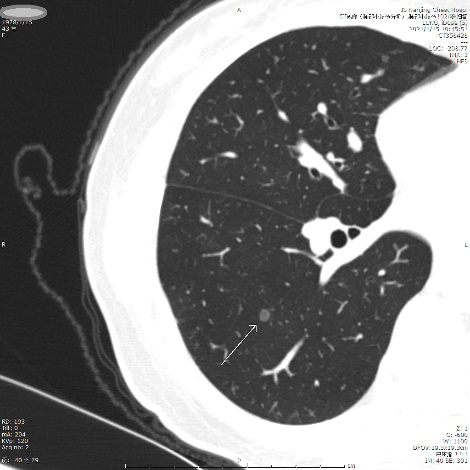

案例二 混杂型结节